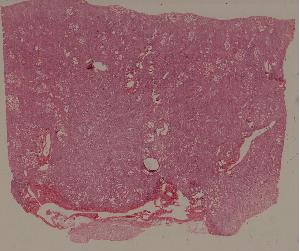

75. Chronic glomerulonephritis

低倍视野